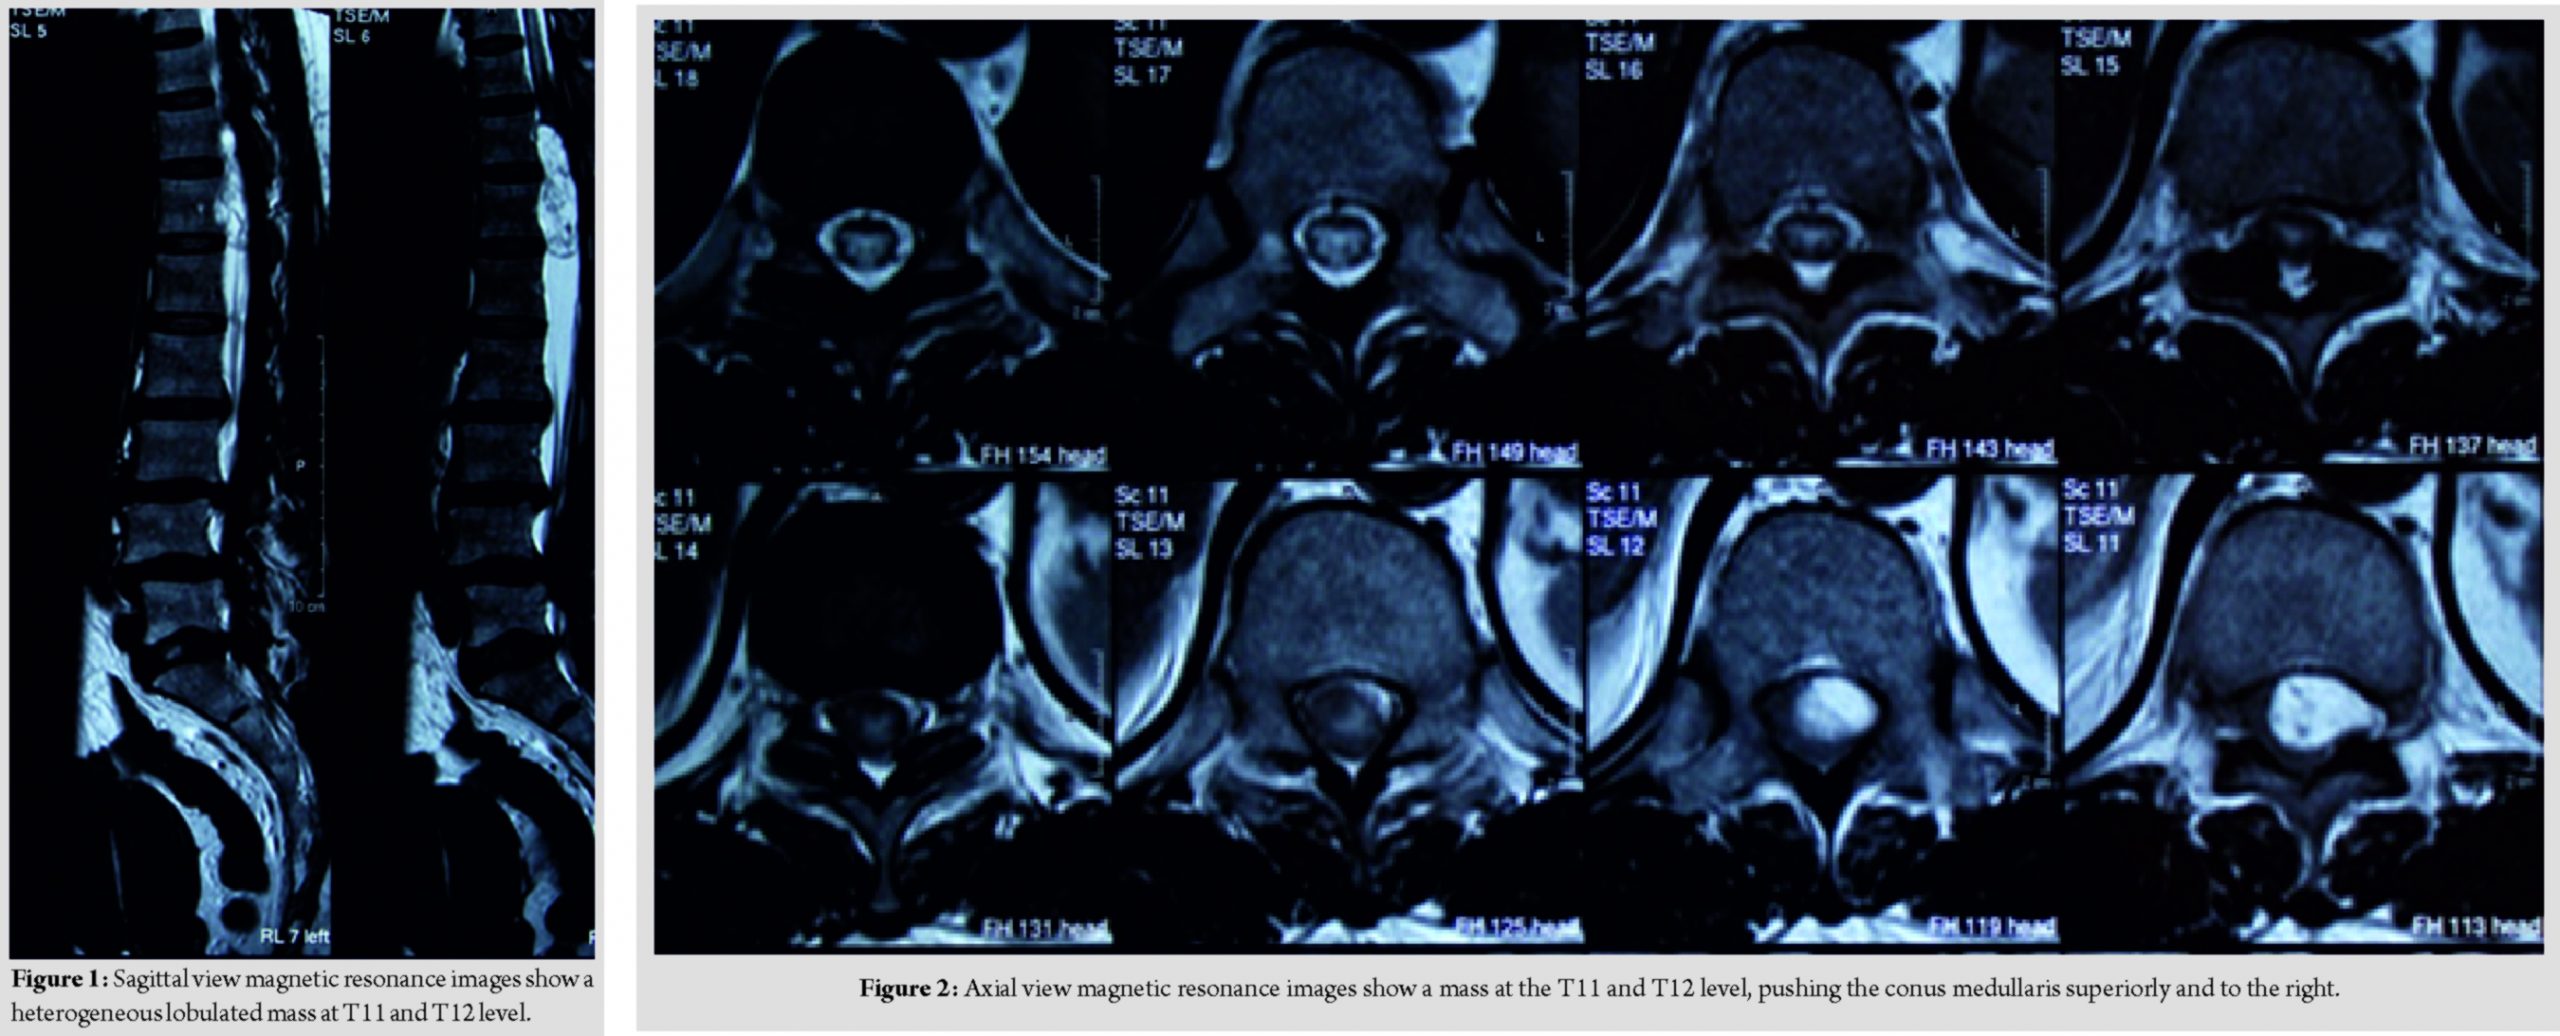

A 57-year-old female lady presented with complaint of sudden onset of urinary incontinence for 3 days duration. Further, history taking reveals that she has been having radiculopathy pain and bilateral lower limb weakness for a year duration. Clinical examination reveals that bilateral lower limb hypotonia, bilateral lower limb motor power of Medical Research Council (MRC) Grade 2, and bilateral lower limb reflexes were absent and sensory reduced from T11 dermatome onward. Magnetic resonance imaging reveals a heterogeneous lobulated mass in the spinal canal at T11 and T12 level, compressing and displacing the conus medullary superiorly and to the right (Fig. 1 and 2).

She underwent laminectomy of T11 and T12 with microscopic assisted excision of the tumor. The mass was located intradural extramedullary and was successfully removed completely; however, the nerve root had to be sacrificed (Fig. 3 and 4).